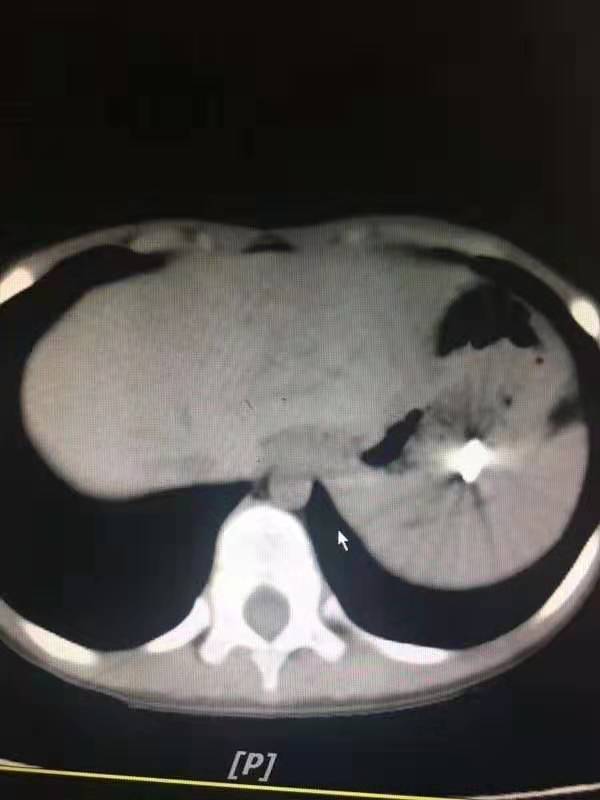

是采取胃镜探查还是腹腔镜探查?刘超医生带着刚刚办好住院手续的孩子做了x线片和CT,还好,钢钉还在孩子的胃里,胃壁没有穿孔。